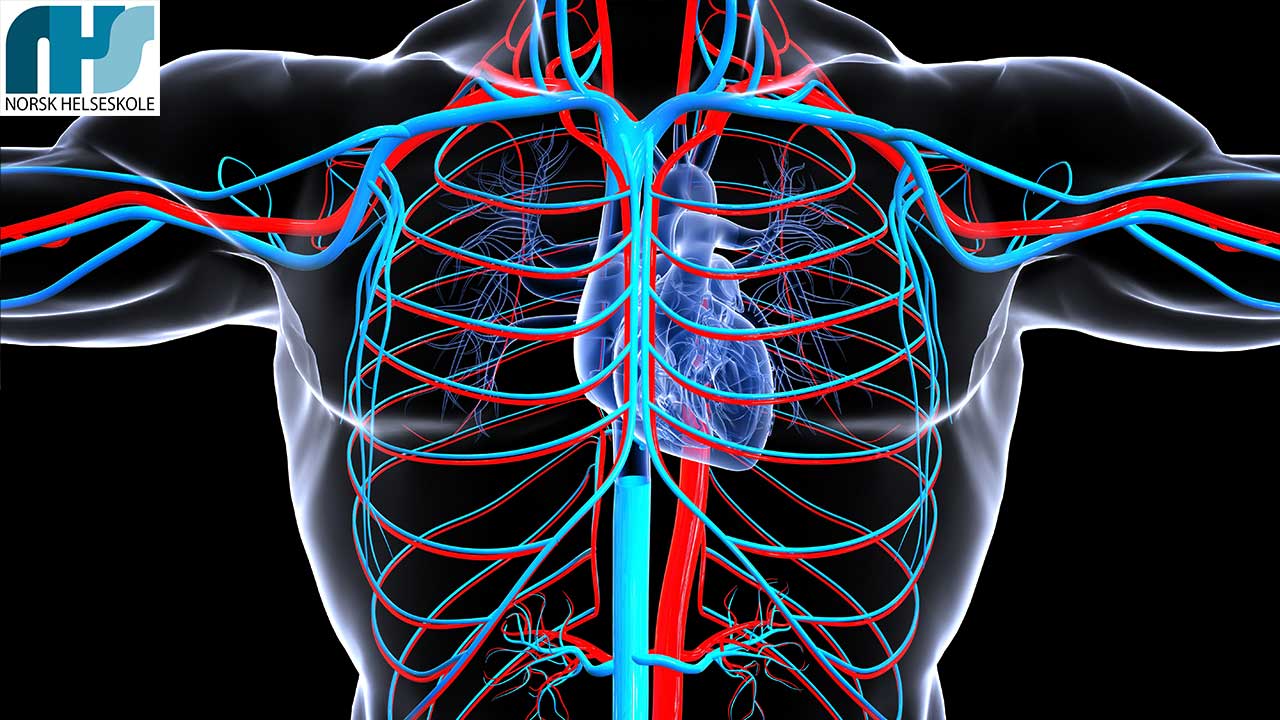

Sirkulasjonssystemet

Sirkulasjonssystemets hoveddeler – Hjertet, blodet og blodårene

Sirkulasjonssystemet, også kjent som det kardiovaskulære systemet, er en integrert del av kroppen vår som holder oss i live ved å sørge for kontinuerlig blodsirkulasjon. Det består hovedsakelig av hjertet, blodet og blodårene.

Hjertet, som er sentrum av dette systemet, fungerer som en kraftig pumpe med fire kamre – to atria og to ventrikler – som effektivt pumper blod rundt i hele kroppen. Denne uavbrutte strømmen av blod sørger for tilførsel av oksygen og næringsstoffer til hver eneste celle i kroppen, samtidig som det fjerner avfallsstoffer.

Blodårene er de intrikate kanalene som transporterer blodet. De kan videre deles inn i arterier, vener og kapillærer. Arterier er store blodårer som fører blod vekk fra hjertet og ut i kroppen. De transporterer oksygenrikt blod, bortsett fra lungearterien som fører oksygenfattig blod til lungene for å hente nytt oksygen. Vener, på den andre siden, fører blodet tilbake til hjertet. De transporterer hovedsakelig oksygenfattig blod, med unntak av lungevenen som bærer oksygenrikt blod fra lungene til hjertet. Kapillærene er de minste blodårene og fungerer som bindeledd mellom arterier og vener. Her skjer utvekslingen av oksygen, næringsstoffer og avfallsstoffer mellom blodet og kroppens celler.